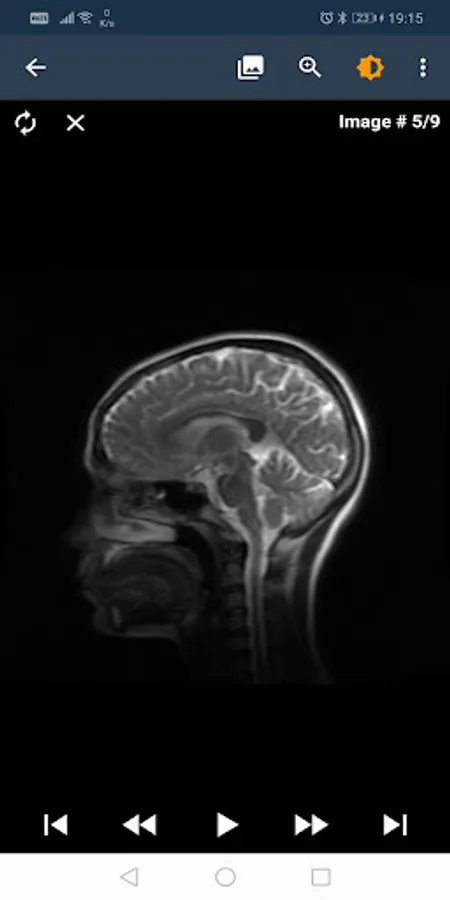

T. C. The Telemedicine System of the Ministry of Health is a system that allows access to the images of radiological examinations on a 7x24 web environment, reporting these images, making teleconsultations between radiologists, evaluating medical images and reports in terms of quality and sharing them with citizens via e-Pulse application.

Radiological Reporting

Radiologist workload distribution between hospitals was balanced and the aim was to provide faster reports to patients.

Quality control

It is aimed to continuously increase the quality of radiology services by regularly monitoring the images and radiological reports taken throughout the country.

the teleconsultation

It is possible for radiologists to reach a more accurate diagnosis by consulting the physicians in the top specialties.